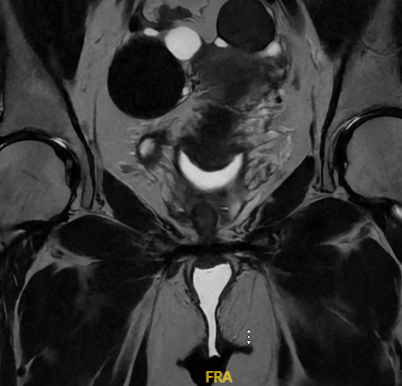

Justo me acaban de mandar un mail con los resultados de mi resonancia... Me encanta que lo tomamos con mucho humor y se hace más llevadero. 😆

No entendemos el informe porque tiene muchas palabras técnicas, pero mañana me verá el doctor de nuevo. 🫡

¿Ustedes que forma ven? 😅

Yo veo un murciélago, un diavlo y una paleta payaso.

Español